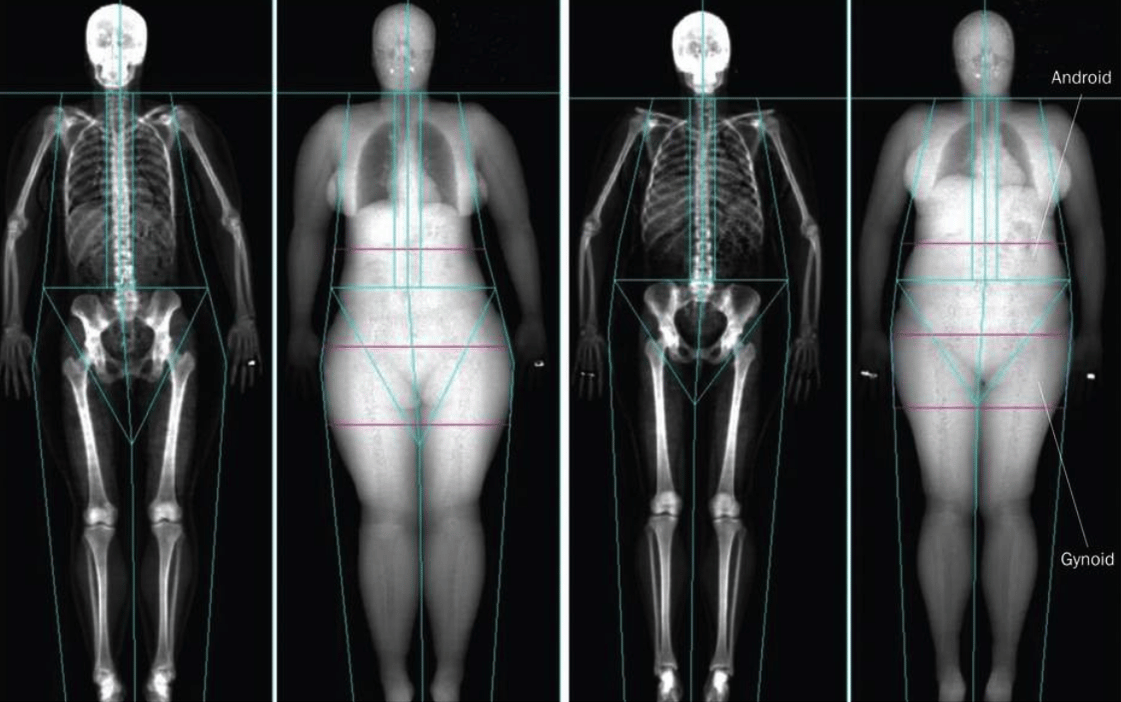

TBM is a short scan performed on a DEXA scanner, which accurately measures the ratio of fat to muscle in your body

- Fat distribution throughout the body including legs, trunk, abdomen and waist/hips.

- Proportion of your body that is fat v muscle v bone.